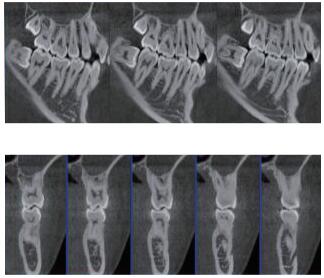

三維重建任意斷層

專有三維重建算法,可提供任意位置高清斷層影像。

專有圖像處理軟件

專有圖像校正技術,去除金屬偽影,提高圖像分辨率。

多平面組合重建

可同時觀察軸向面、冠狀面和矢狀面圖像,方便臨床診斷。